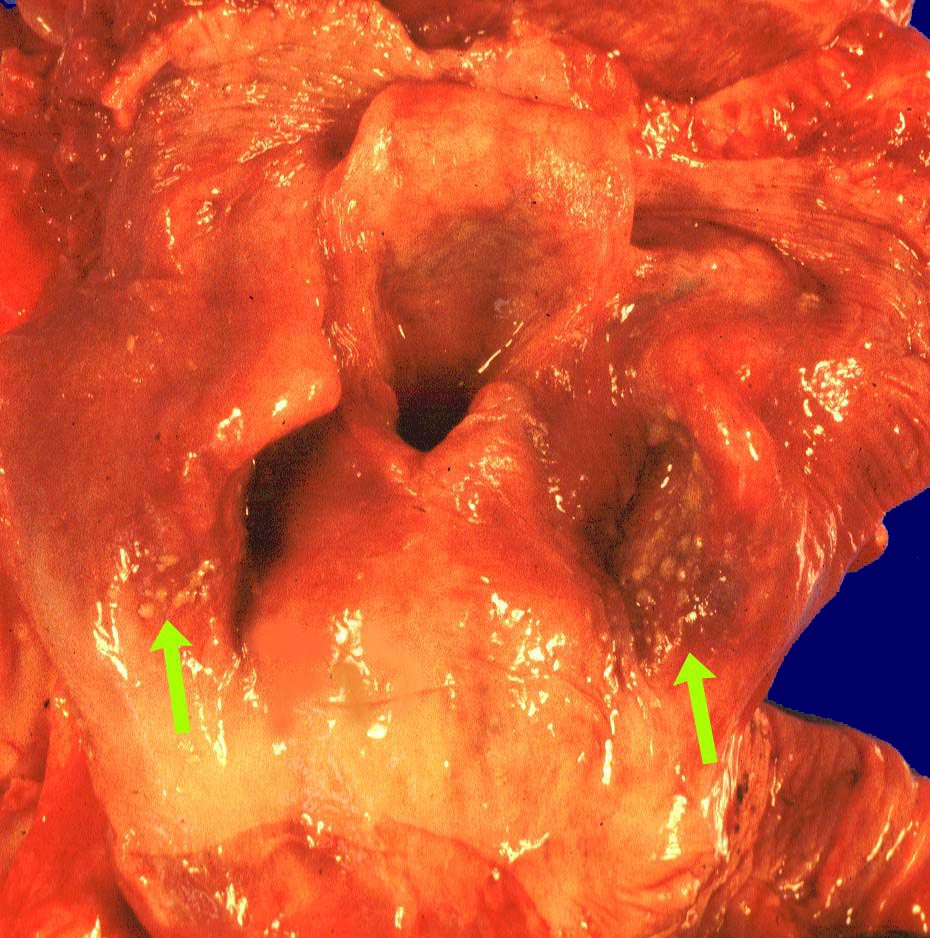

Soorösophagitis

Entzündung infektiös

Oropharynx

Oropharynxschleimhaut mit runden, leicht erhabenen Auflagerungen.